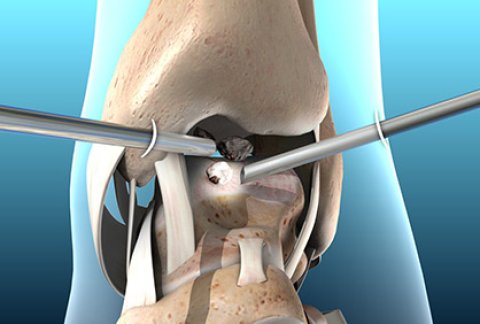

What is keyhole surgery? And what are its benefits?

Keyhole surgery, a term used colloquially to describe minimally invasive procedures, ...